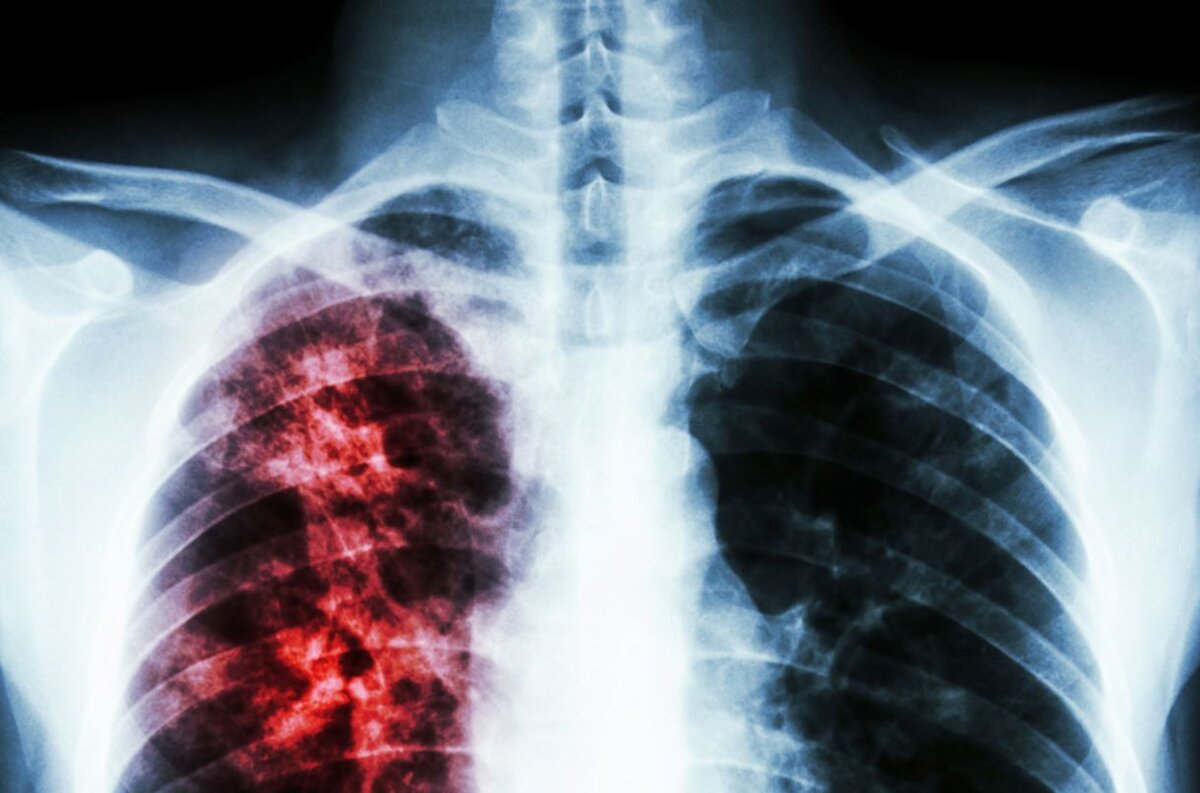

Как определить туберкулез на ранней стадии

По словам врача, данные симптомы (не обязательно все сразу) — это повод обратиться к врачу и провести рентгенологическое обследование органов грудной полости. "Длительно протекающий воспалительный процесс без должной динамики от лечения — это показание для осмотра фтизиатра", — пишет Елена.